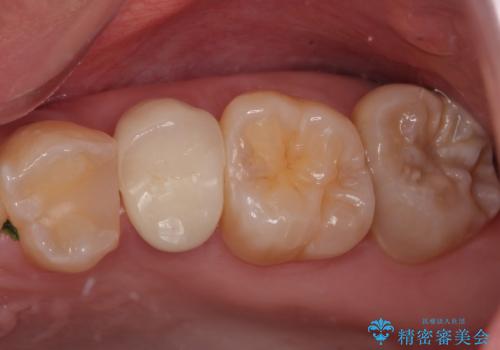

- 左上の前から5番目の金属の詰め物(メタルインレー)が取れたとのことで来院された患者様です。一時帰国中とのことで短期間での治療を希望されていました。土台はファイバーコアがしっかり入っていたため、そのまま利用することにしました。根管治療は症状もなく、レントゲン上でも病変を認めないため患者様と相談して根管治療を行わないことにしました。拡大鏡の視野下において、虫歯を除去して元々の詰め物の範囲も大きいためオールセラミッククラウンに適した形に整えました。

型どりは、シリコーン印象材にて印象しています。

適合もよく、機能的に問題もなく、見た目も満足されていました。